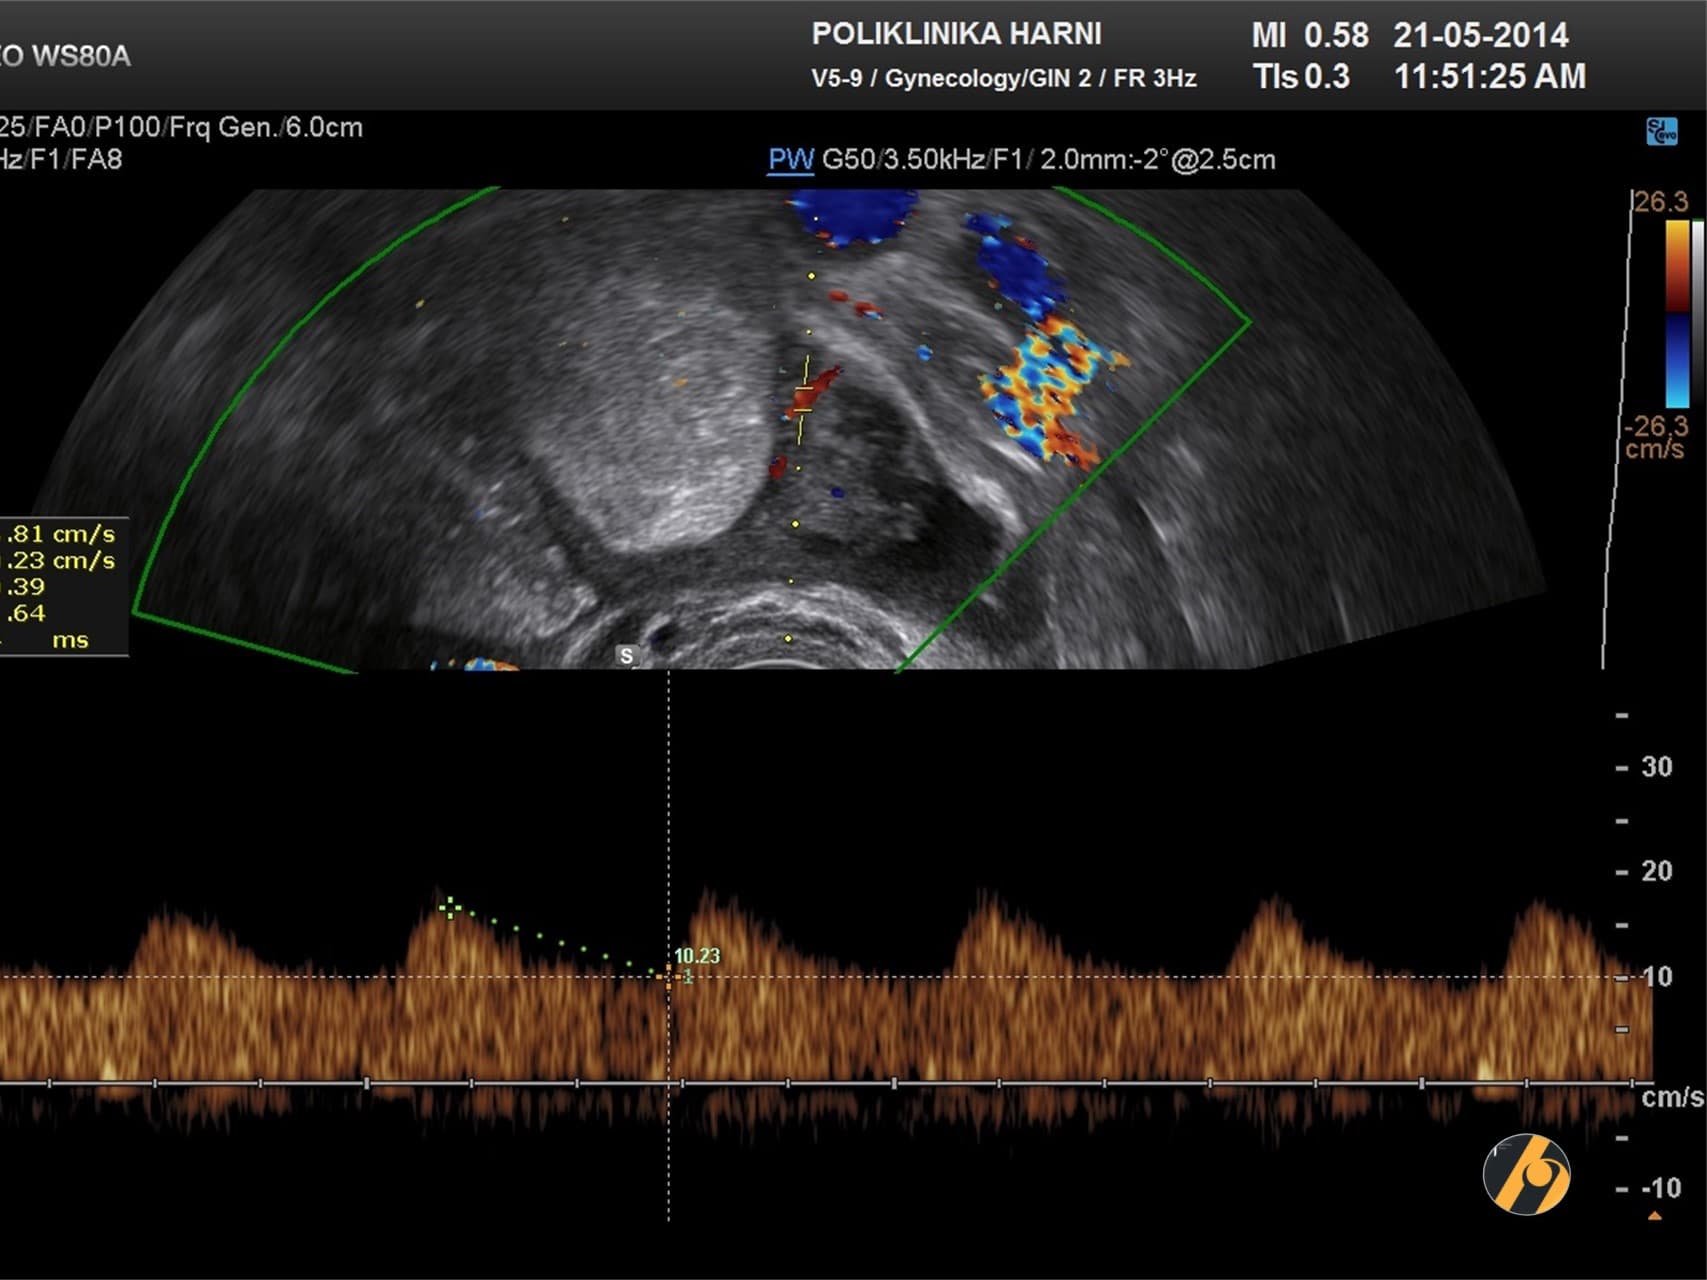

Pri ultrazvučnoj analizi ponašanja tumora od najvećeg značaja su procjena nepravilnosti u morfologiji i ehogenosti, kao i pojava novih krvnih žila - proces neovaskularizacije.

Stvaranje novih krvnih žila je zajednički fenomen svih malignih neoplazmi jajnika, ali je intenzitet neovaskularizacije ovisan o karakteristikama individualnog tumora. Otuda i pad otpora protoku krvi kroz krvne žile tumora može biti pokazatelj tumorskog malignog potencijala.

Najučinkovitija tehnika u procjeni neovaskularizacije samog tumora, kao i područja u njegovoj neposrednoj okolici je tehnika obojenog Dopplera i osobito 3D power Doppler ultrazvučna tehnika. Mogućnost pažljive analize arhitektonike krvnih žila tumora značajno poboljšava i proces ultrazvučne dijagnostike raka jajnika. Malignu neovaskularizaciju odlikuju mnogobrojni arteriovenski shuntovi - spojevi između arterijskih i venskih krvnih žila, suženja ili mikroaneurizme i slijepa krvna jezerca. Tako i točnost postavljanja ispravne dijagnoze raka jajnika u njegovom najranijem stadiju primjenom kombinirane metode višedimenziolanog ultrazvuka s osnaženim doplerom iznosi 97.7%.